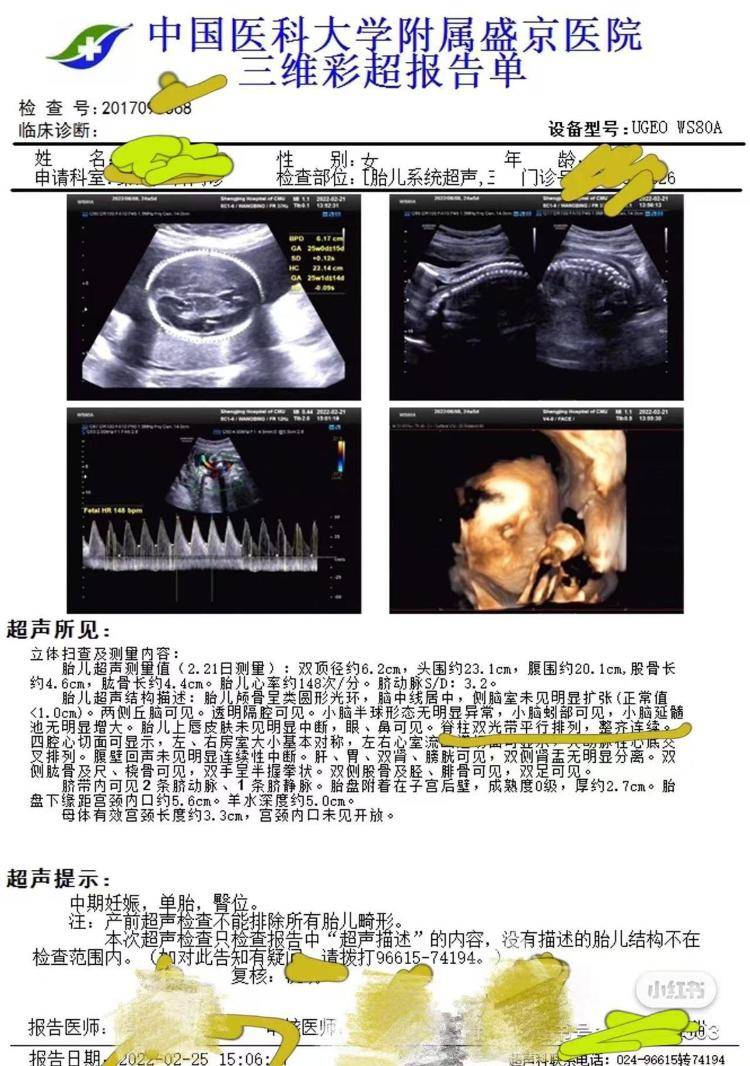

3月11日,高女士告诉极目新闻记者,2021年10月,她到盛京医院做了第一次产检并预约了后续的检查,2022年2月25日,她在盛京医院做了包括胎儿系统超声在内的大排畸检查,检查结果显示胎儿“脊柱双光带平行排列,整齐连续”,2022年6月15日,女儿出生。同年12月,女儿在核磁检查时被确诊脂肪脊髓脊膜膨出和椎管内脂肪瘤,即“脊柱裂”,“脊柱裂意味着女儿后期需要多次手术治疗,否则会足踝畸形、大小便失禁,严重的话甚至会导致下半身瘫痪。”

产前彩超显示胎儿脊柱正常(受访者供图)